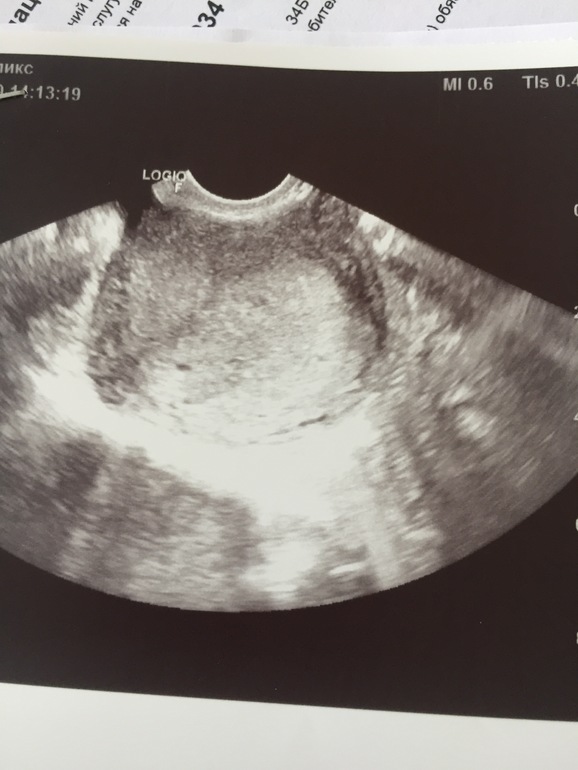

Ходила на узи

Совсем маленький срок , повторно пойду через две недели и уже можно увидеть эмбрион и услышать сердцебиение , Беременность маточная все хорошо )))